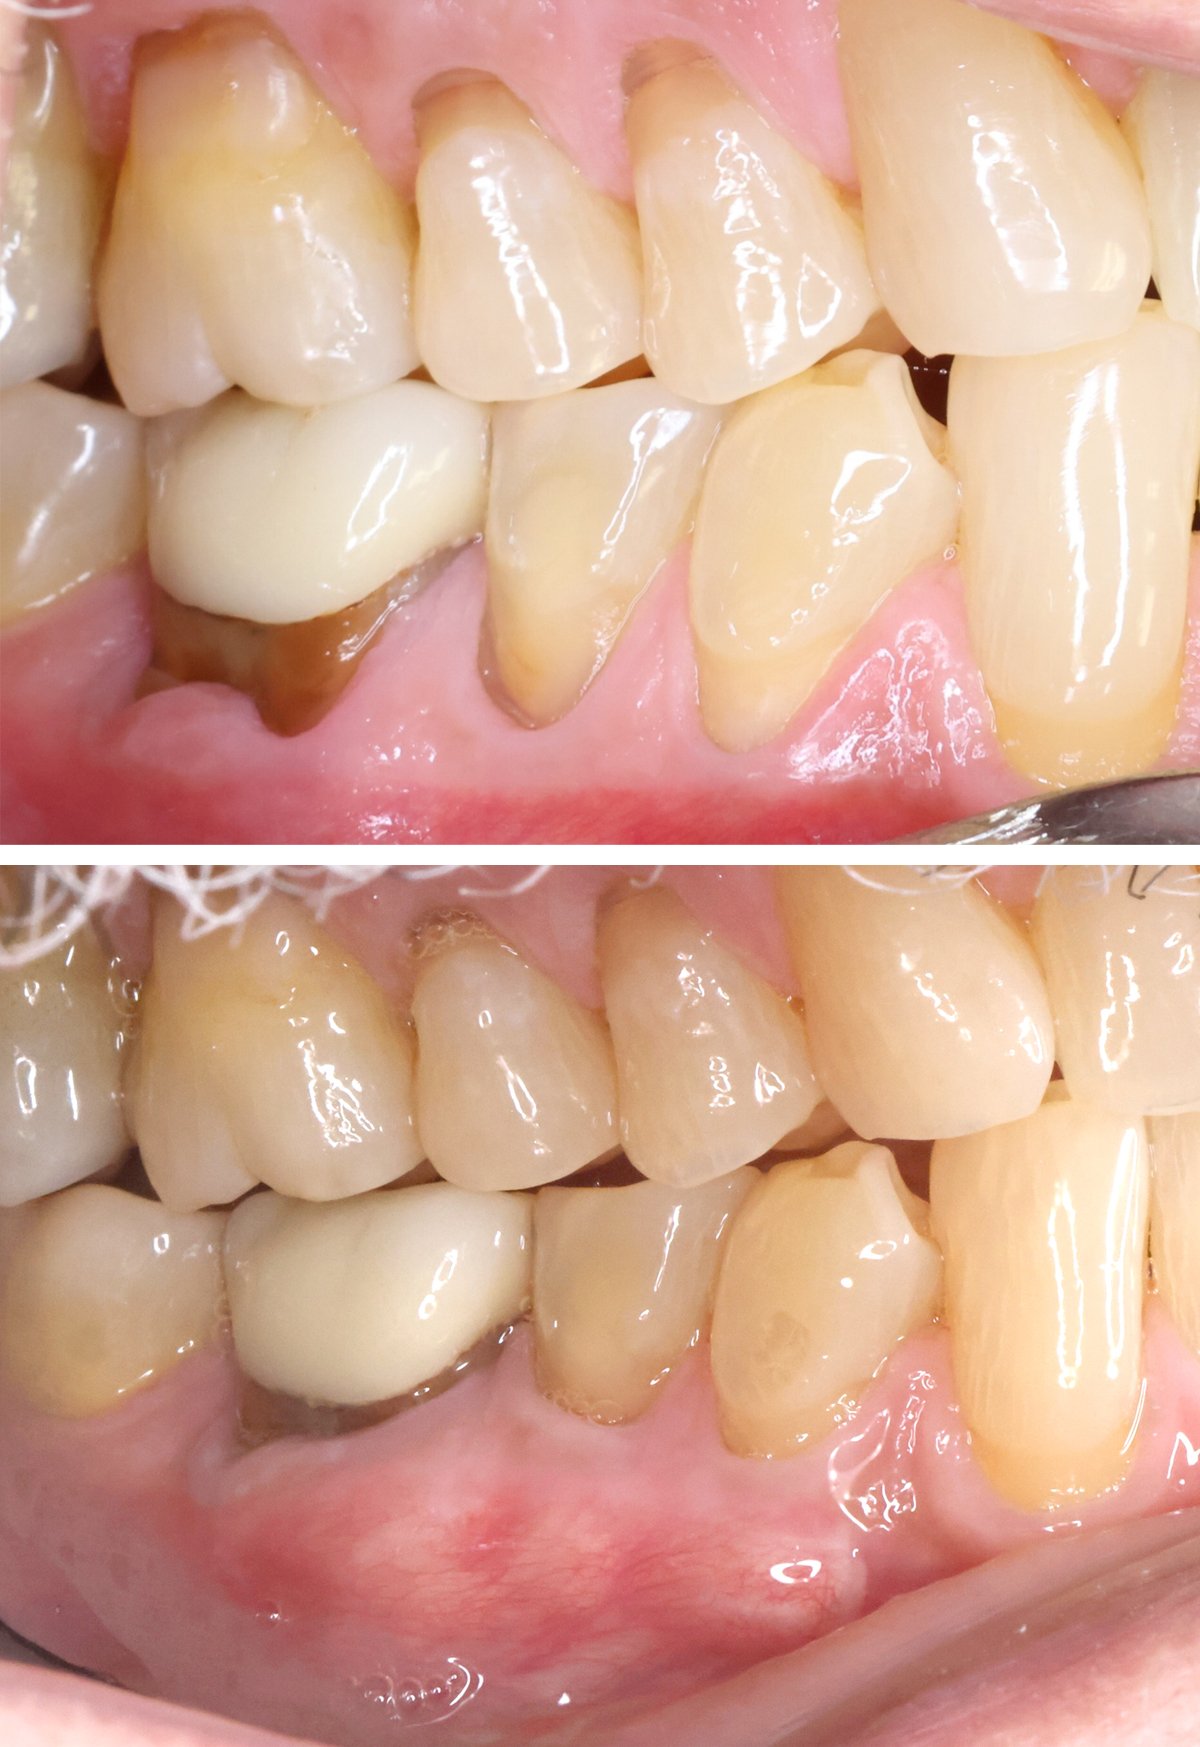

Soft Tissue Graft

We treat gum recession to enhance aesthetics, strengthen gum tissue, and provide better long-term support for teeth and dental implants.

Free Gingival Graft

Free Gingival Graft (premolars)